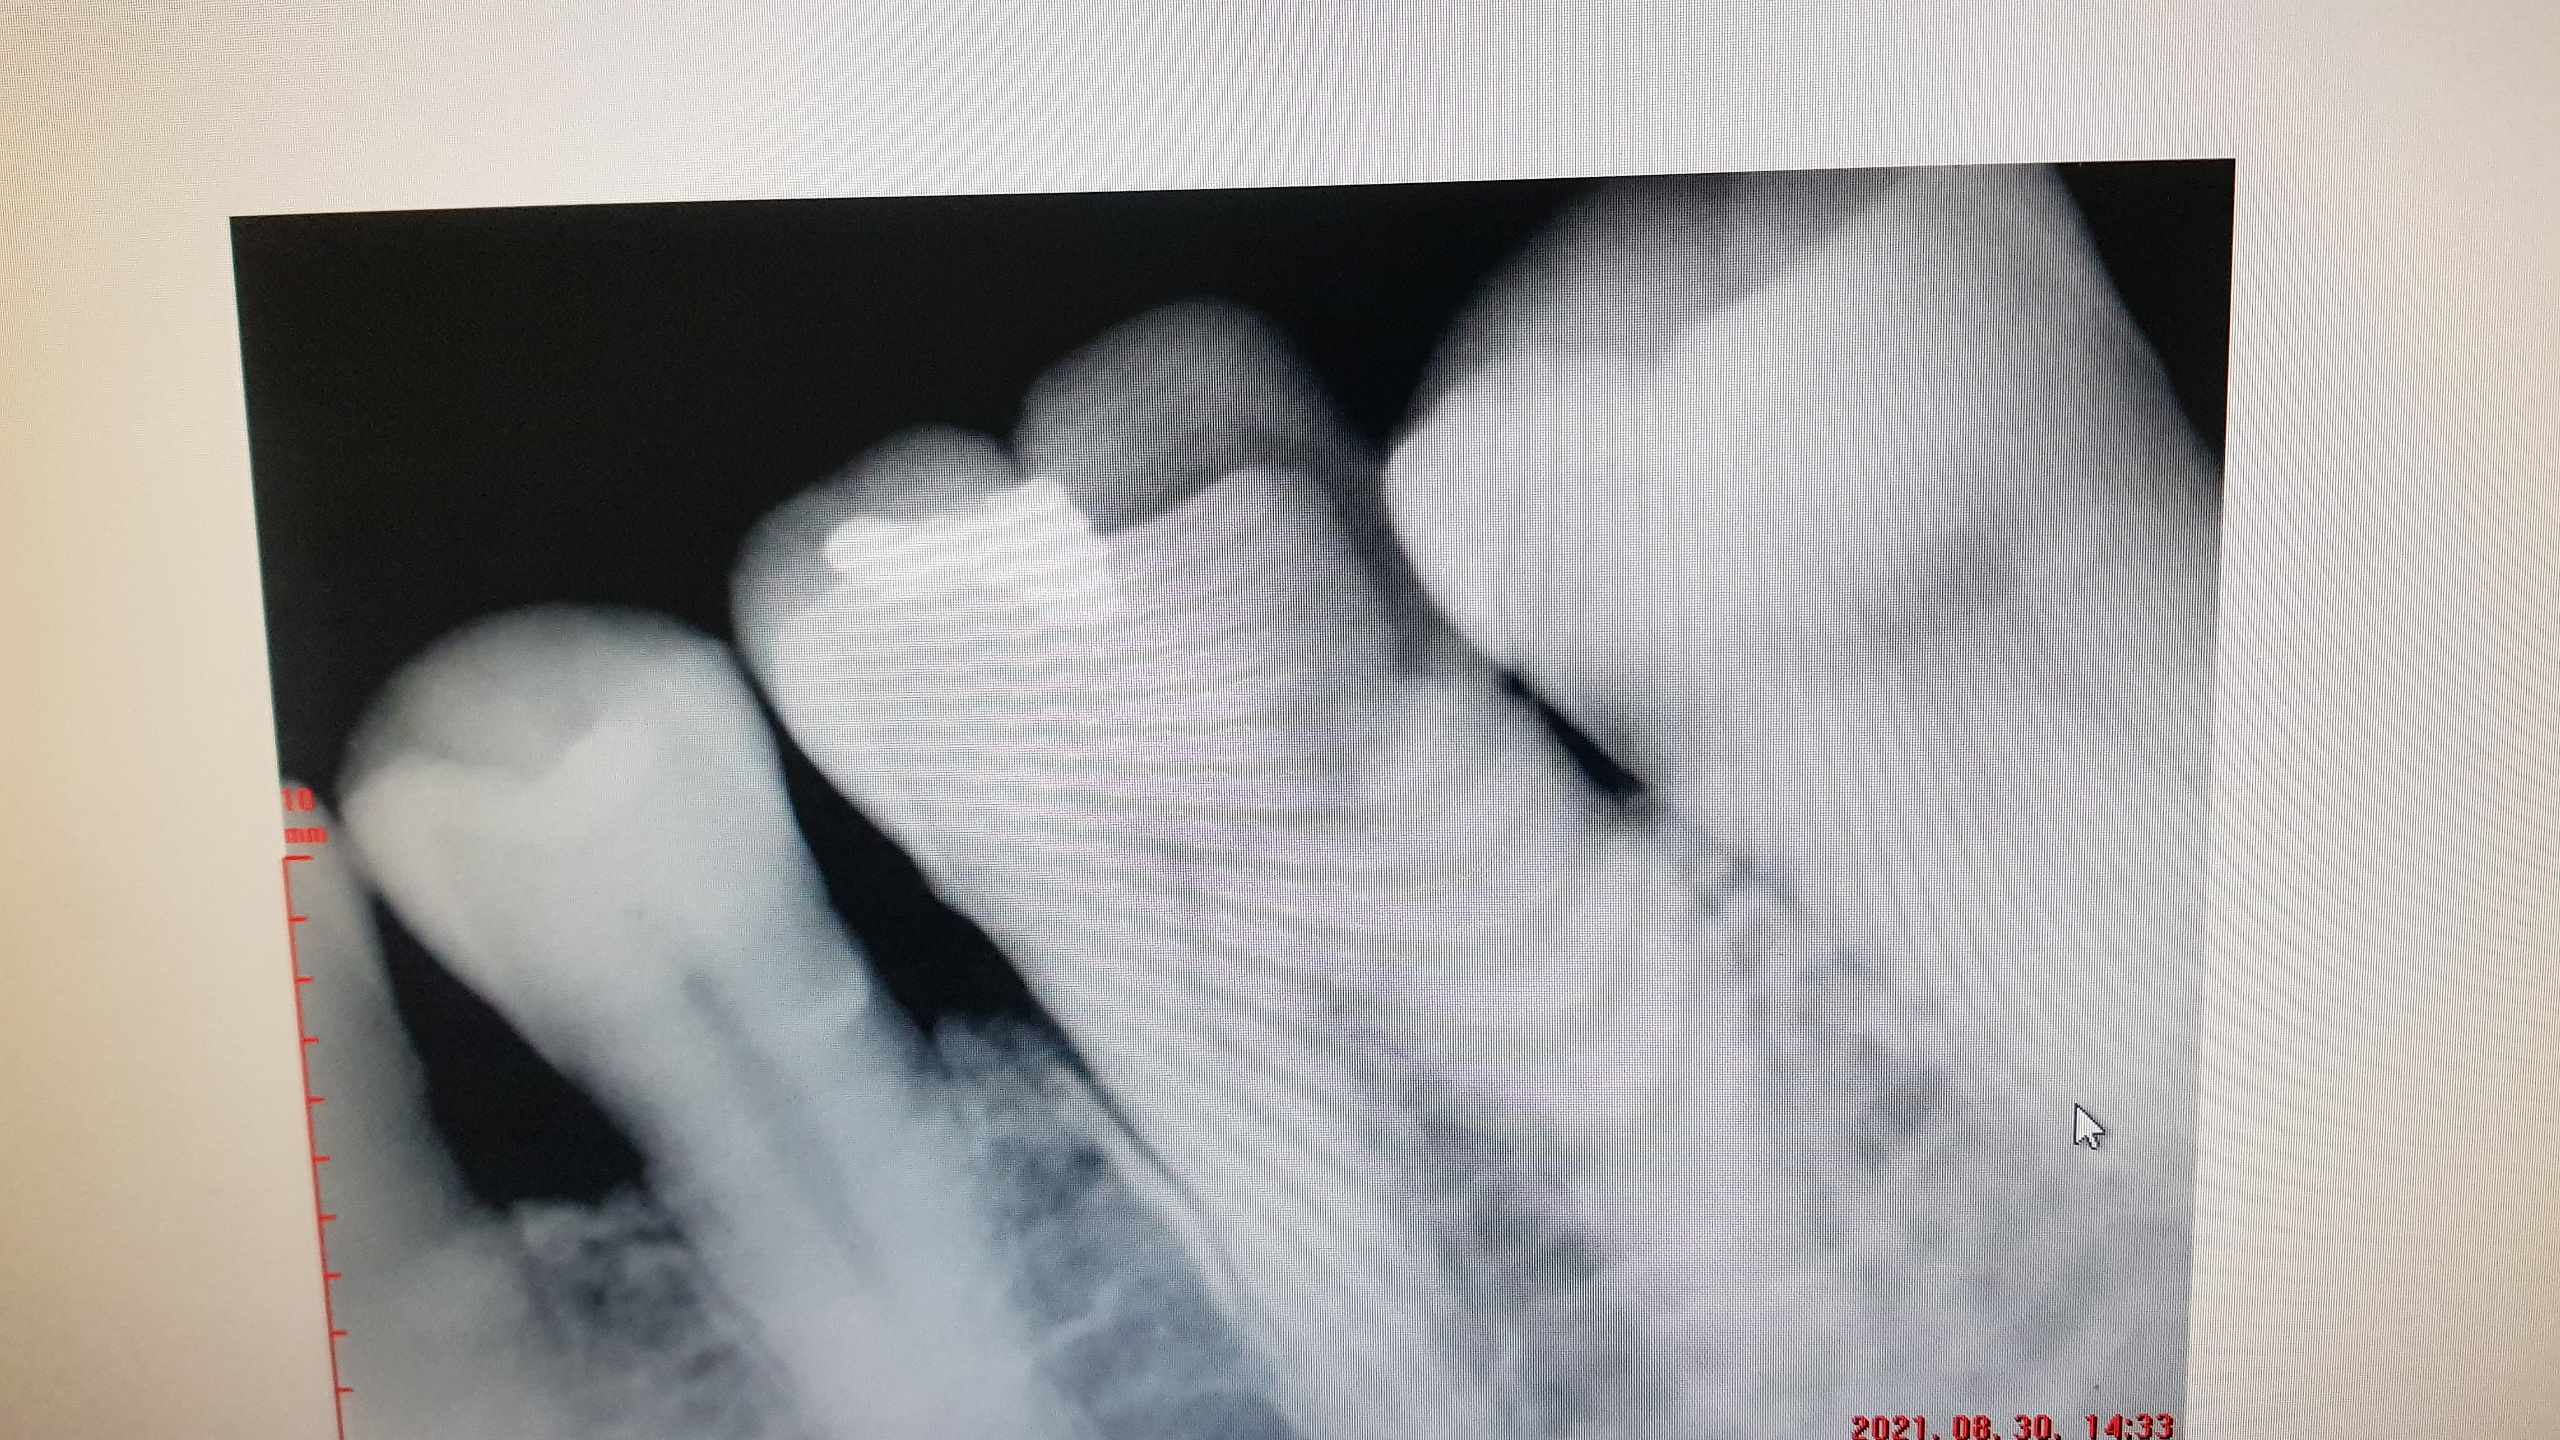

일단 ..또다시 엑스레이를 찍고..

여기서도..신경 치료를 해야한다고 한다.